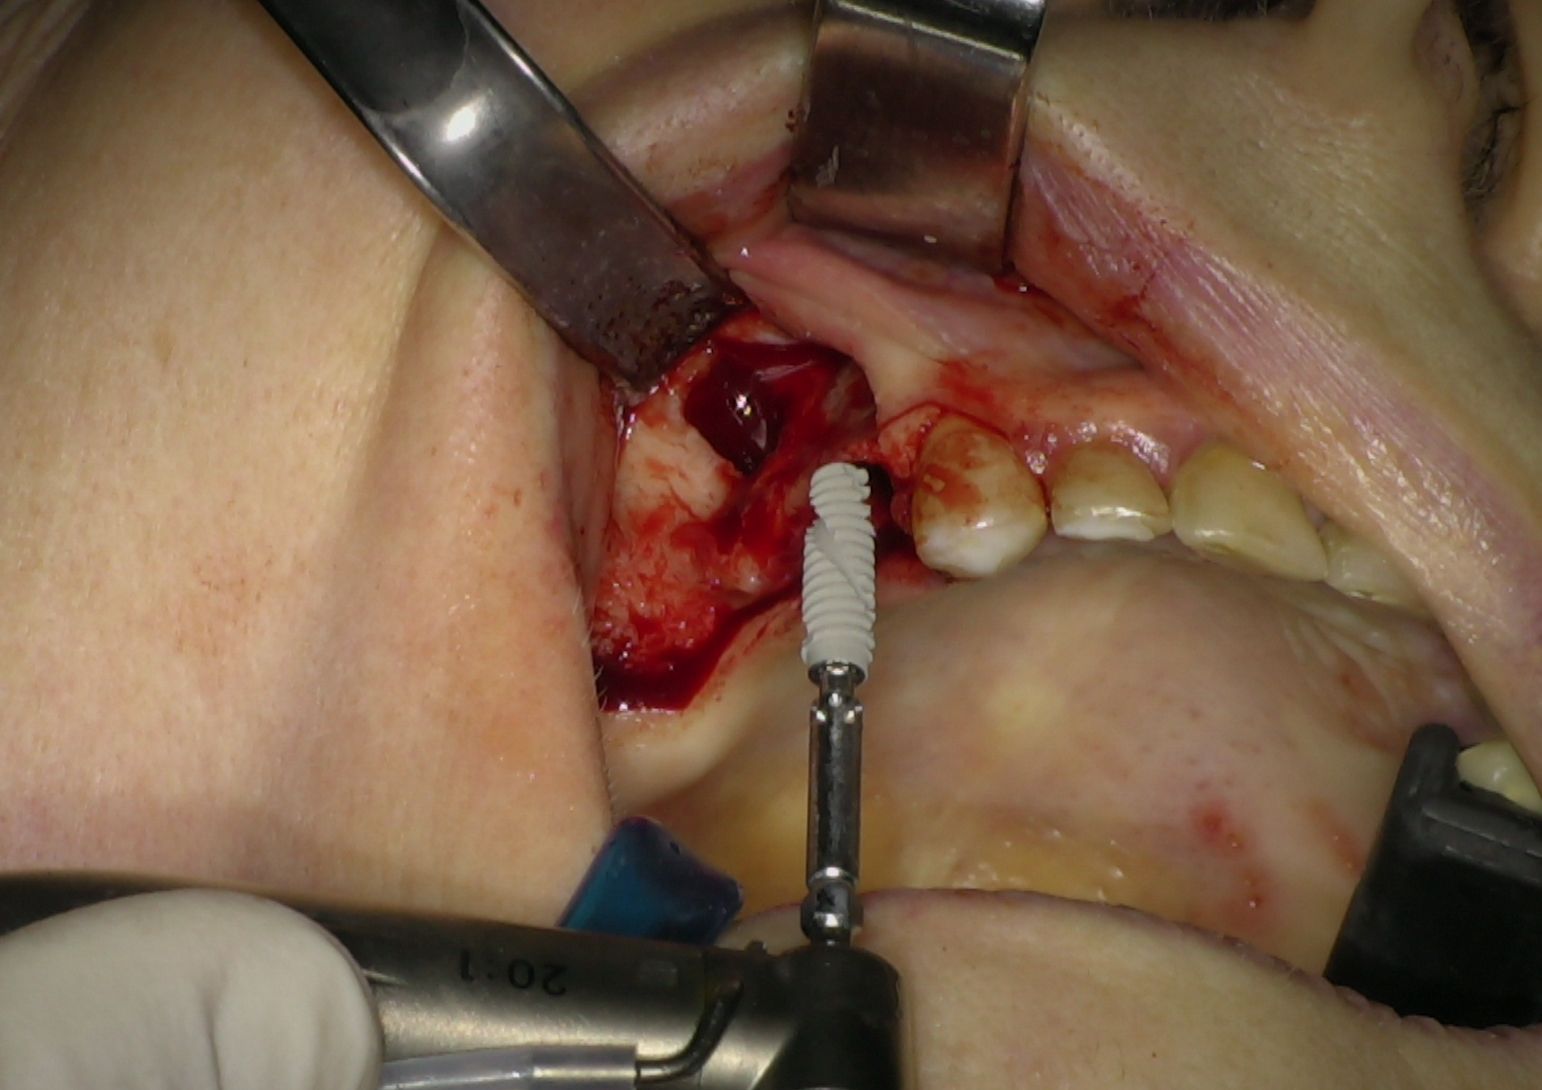

L'intervento chirurgico è stato eseguito in anestesia locali. Dopo il sollevamento di un lembo musopeiosteo a tutto spessore per esporre il mascellare, nei settori anteriori si è proceduto con la preparazione dei siti implantari secondo protocollo convenzionale. Gli impianti IS+ sono stati quindi posizionati (Fig. 2), ottenendo una buona stabilità primaria grazie alla presenza di un adeguato volume di osso residuo.

Fig. 2 - Impianti IS+